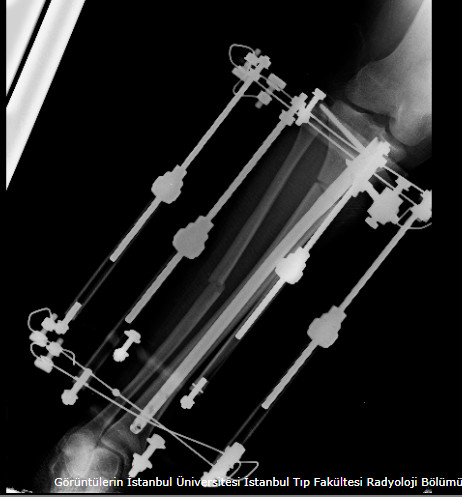

Lengthening SurgeryDec 30, 2021 | Case Examples Case 1: Tibiada Extension Over Nail (LON) Case 2: Femurda Extension Over Nail (LON Case 3: Femurda Automatic Nail Extension